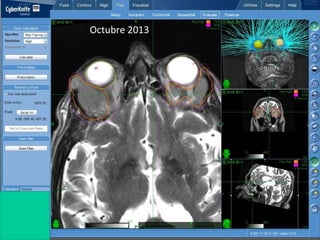

56 años Meningioma OMS I

2 Neurocirugìas Previas

Radioterapia Conformal previa

Deficit de Par craneal IV-VI-III

Dolor Neuralgico Trigeminal

Fotofobia - Epifora

Radiocirugia de Salvamento

octubre 2012

Control local 100% por RNM

Asintomatica

56 meses

PosRadiocirugía

Robótica

Cyberknife